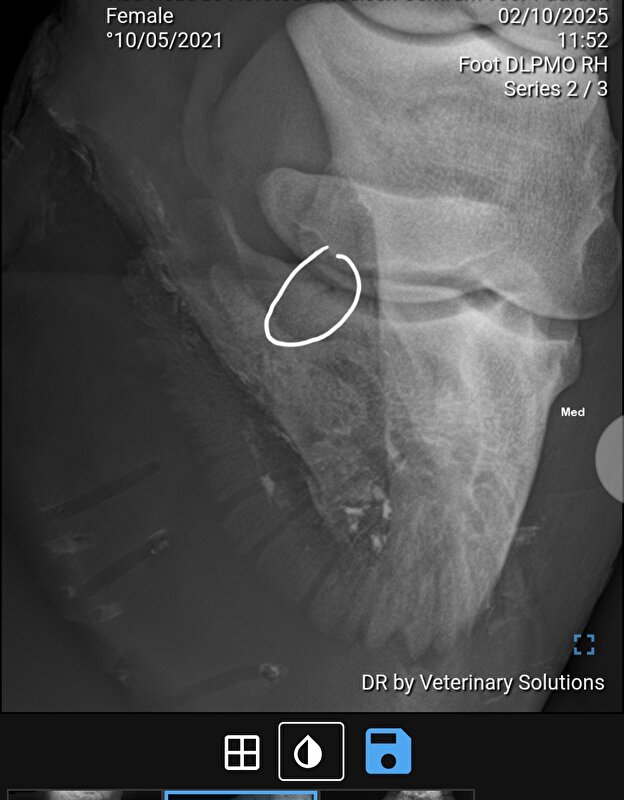

Die van mij mocht na 6 maanden stalrust (wel echt op stal, en ook een rond ijzer) weer naar buiten. Ging toen ook over op een normaal ijzer. Zijn wel na zo'n 2,5e maand weer begonnen met stappen ad hand. Uiteindelijk heeft ze door een operatie aan mijn kant in totaal 8 maanden op "stal"rust gestaan (laatste 2 maanden in de opfok in een stal van 5x10m). Na 8 maanden de laatste foto's gemaakt, ijzer is er compleet onderuit gegaan, naar buiten toe opgebouwd (had dus al 2 maanden eerder gemogen maar ging niet op de stal waar ze toen stond) en sinds 1 november staat ze eindelijk weer op een normale pensionstal.

We hebben hier wel de 6 maanden volgemaakt en ik heb in het proces nog een keer een second opinion aangevraagd maar die gaven eigenlijk hetzelfde aan. Maar het zal wrs ook afhankelijk zijn van de grootte en de plek van de breuk en hoe vlot het hersteld.

Het gelaste tussenstuk was er tussenuit. Heb toen wel extra foto's laten maken maar dat zag er gelukkig goed uit. Dus het "kon wel wat hebben". Daarna ruim 3 maanden in de opfok, vond mn portemonnee wat prettiger

Liep hier alleen helaas wel door tot het gewricht

Ben zelf dus vooral bang voor potentieel artrose op "jongere" leeftijd maar ook de second opinion was heel tevreden over de genezing dus hopelijk valt dat mee

DA heeft daar verder ook weinig over gezegd maar dat is echt iets wat de tijd uit zal moeten gaan wijzen. Dat die van jou dat niet heeft klinkt iig gunstig! Alhoewel ze bij jou miss wat sneller bang zijn dat dat hoekje kan gaan "verschuiven"?